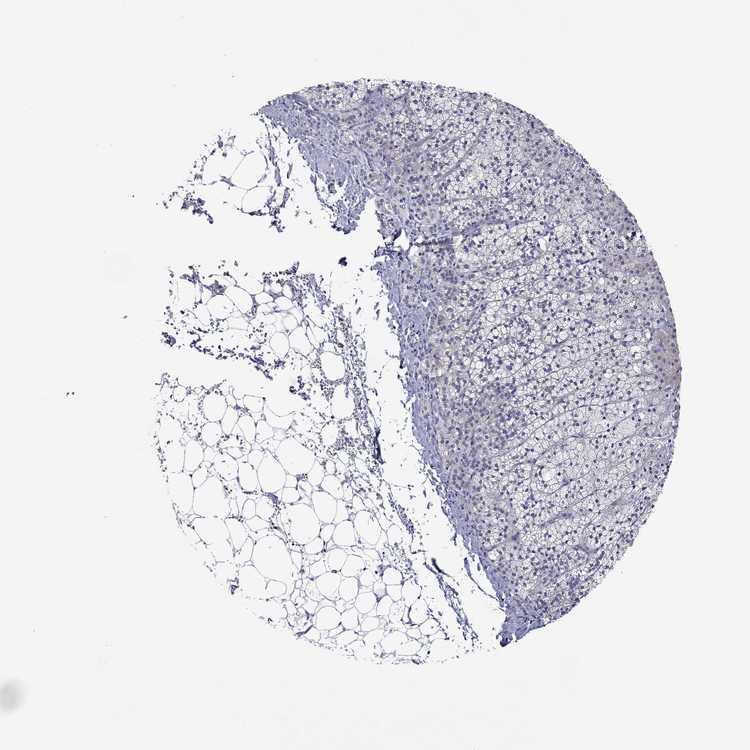

ADRENAL GLAND - Antibody stainingi

Antibody staining in the annotated cell types in the current human tissue is reported as not detected, low, medium, or high, based on conventional immunohistochemistry profiling in selected tissues. This score is based on the combination of the staining intensity and fraction of stained cells.

Each image is clickable and will lead to virtual microscopy that enables deeper exploration of all samples and also displays staining intensity scores, fraction scores and subcellular localization as well as patient and tissue information for each sample.

Antibody HPA038891

Glandular cells Not detected